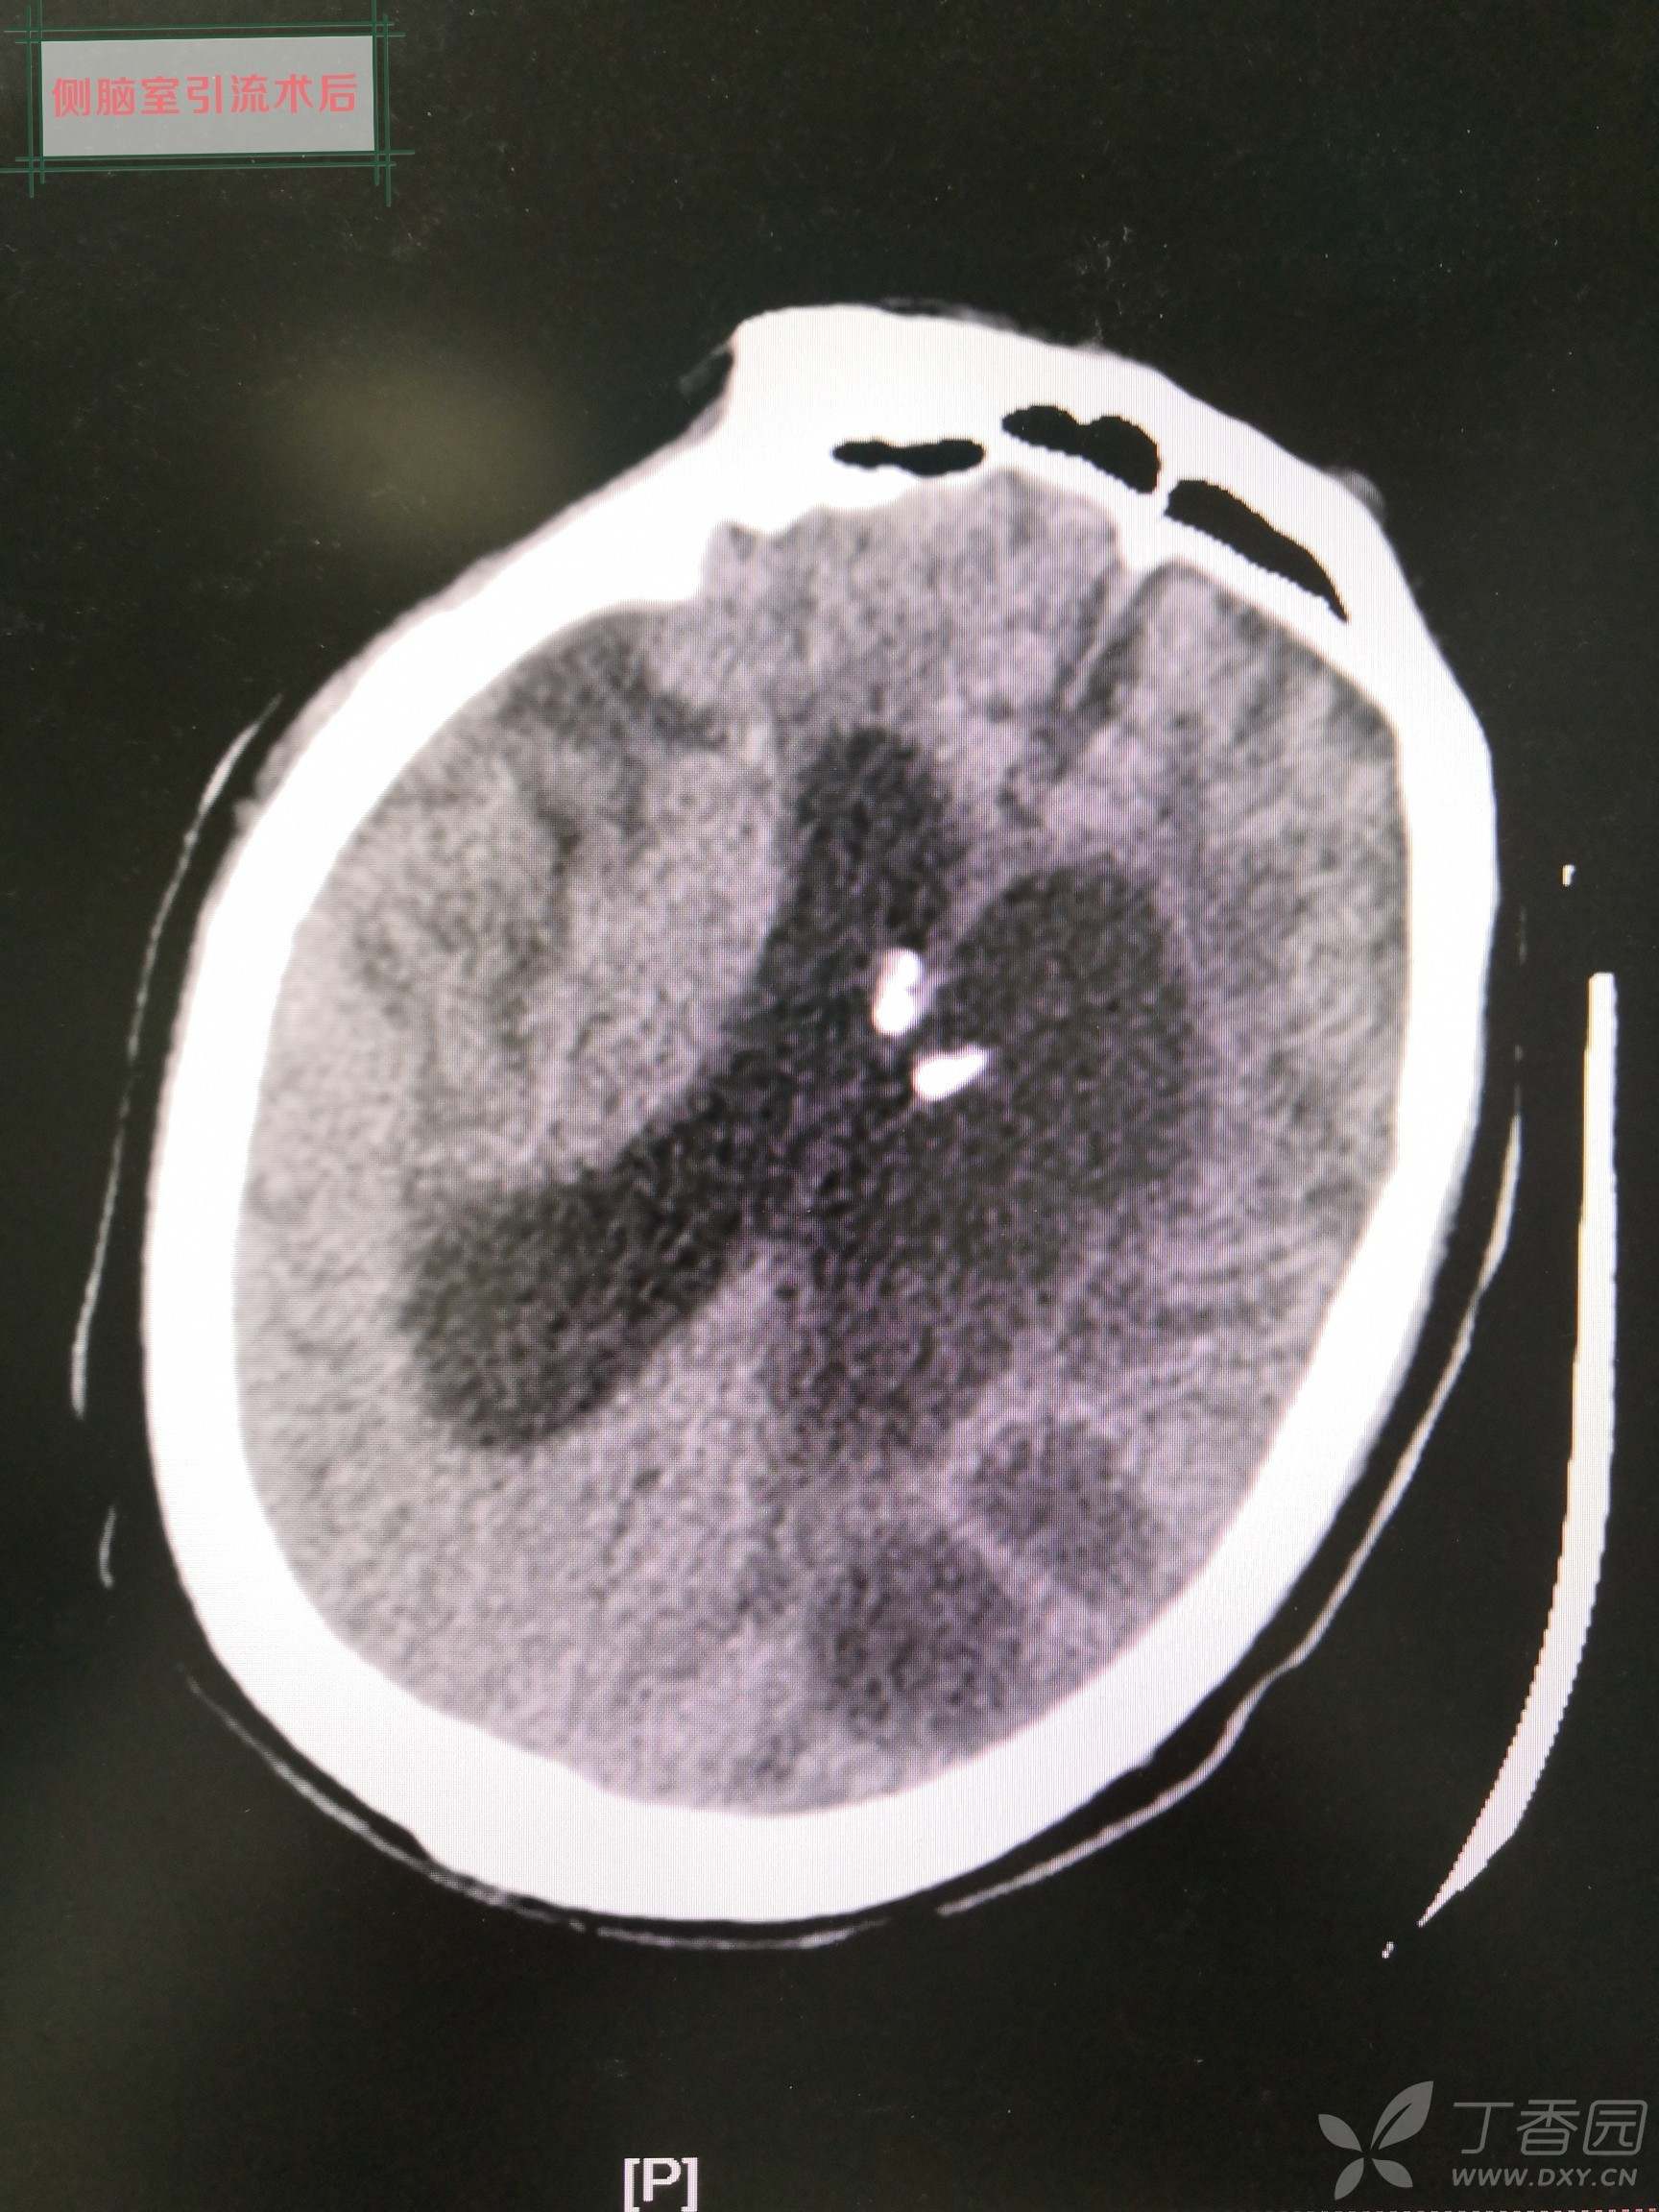

侧脑室引流术后复查CT: